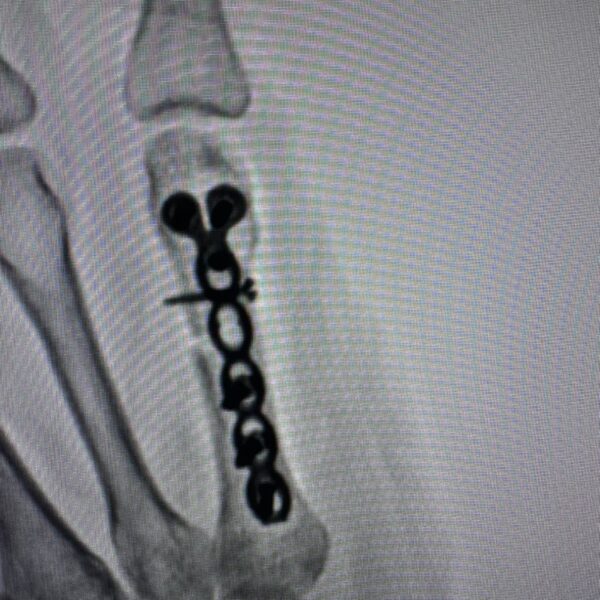

Moments That Mark Meaningful Recovery

Witness real patient transformations at The Ortho Clinic through images that reflect successful treatments and restored mobility.